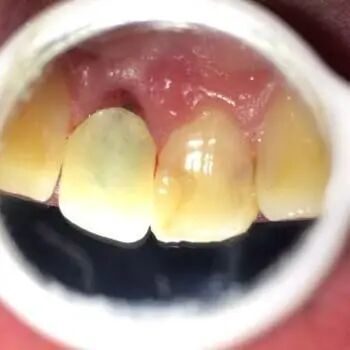

继发龋齿是在龋病治疗后,由于充填物边缘或窝洞周围牙体组织破裂,形成菌斑滞留区,或修复材料与牙体组织不密合,留有小的缝隙或存在微渗漏,或原有的病变组织未除净就进行充填,这些都可能形成致病条件,再发生龋病,称继发龋。

因为继发龋位置比较隐蔽,有时候它可能在充填材料旁边,有时候可能充填材料下面,有时候还可能在充填材料里面,所以它的位置很隐蔽很难发现。